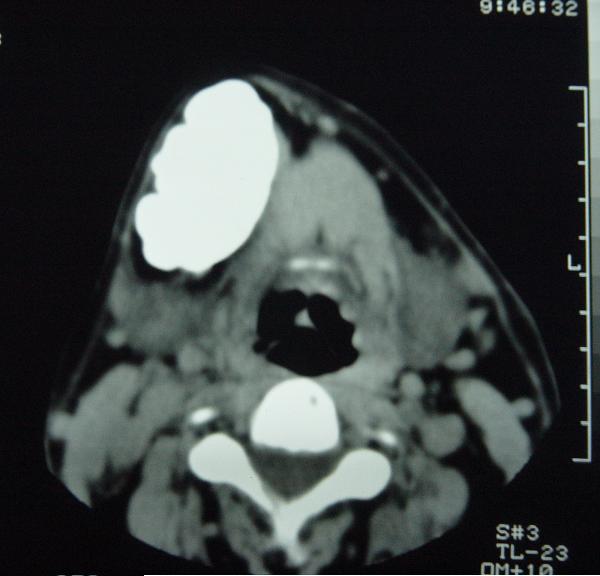

标题: CT12465:下颌骨肿瘤,请会诊 [打印本页]

标题: CT12465:下颌骨肿瘤,请会诊

发现下颌骨肿瘤近30年.逐渐增大.

考虑右侧下颌骨水平部及升部骨纤维异常增殖症可能性大。

造釉细胞瘤,没有特征性;半月切迹?骨间隔?多房性骨密度减低区,大小不等。鉴别;动脉瘤样骨囊肿,骨软骨瘤。本人,更倾向于---骨软骨瘤。

考虑右侧下颌骨骨化性纤维瘤。